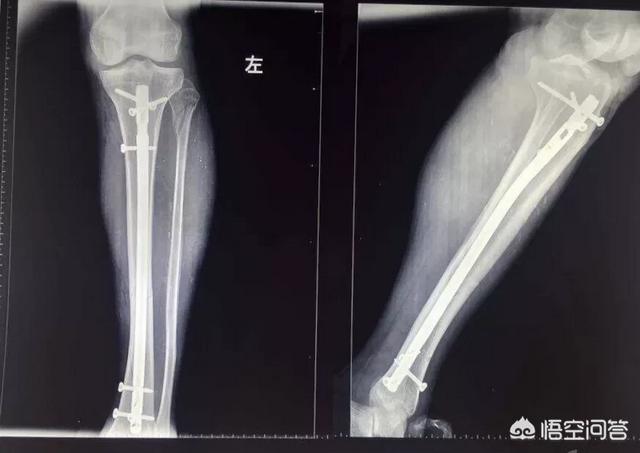

5256脛骨腓骨骨折手術時に挿入されたプレートとボルトの抜釘について 更新 73歳の女性です。 約二年前に脛骨腓骨を骨折、チタンのプレートを入れる手術をしました。 手術後、医師から抜釘はしない、と告げられたましたが、担当医が若い医師に 骨折日記35:脛骨高原骨折抜釘手術をした! 脛骨高原骨折 脛骨高原骨折 本日朝9時から抜釘手術をおこないました。 手術前から終わるまで ①手術する方の足に「ope」と先生がマジックで記入(前日) ②朝ごはん抜きでスポーツドリンク2本(昨年と同じものでした。 1時間前までに飲む) ③血栓予防の靴下をはく ④手術着に着替え ⑤点滴をいれる 時間となり、ここからは写

回, 脛骨高原骨折に対し観血的治療を行った症 例について, その治療方法と術後成績について 検討したので報告する 対象および方法 対象は脛骨高原骨折に対して観血的治療を施 行した9例9関 節である 受傷時年齢は37~86 歳 (平均565歳) であった 脛骨近位部骨折の治療法 保存療法 :骨折が軽傷であった場合、ギプス固定をする 手術 内固定法:割れた骨や骨のかけらを元の位置に戻し、プレート固定を行う 小侵襲内固定術:割れた骨や骨のかけらを元の位置に戻し、プレートやスクリューを使って固定する リハビリテーション:足の筋力の改善、膝の動きを改善する 骨がくっつくまでに12か月かかる場合が多い 骨が弱かったり 脛骨腓骨骨折プレート固定術をするとおおよその目安の期間は以下になります。 (骨折箇所によって安静期間や固定期間は違いますが、今回の足の手術の場合ということで参考までに) 荷重訓練は6週間後から開始(最初は1/3荷重から) ↓ 全荷重が3ヶ月後 ↓ プレートを抜くのは1年後 しばらくプレートは入ったままの生活になります。 プレートのビスは抜けないのか心配 昔は「ビス

骨折から1年と1か月、とうとうプレートとボルトを抜く抜釘手術を受けてきました。 骨折の経緯は下記 アイスクライミングで右足果部 腓骨・脛骨骨折 復帰までの記録 ①受傷から手術~退院まで ムカデのおにいさんのブログ アイスクライミングで右足果部腓骨・脛骨骨折 復帰までの記録ずれがない骨折であれば、ギプス装着を数週間行うことで治癒することが多いとされています。 手術 骨のずれが大きいなどの場合には、骨の位置を正しい位置に戻す手術が必要です。 足関節の骨折では、骨片の配置を正しく整え、また治癒中に再び骨片がずれることのないよう、観血的整復固定術(ORIF)と呼ばれる手術を行うことがあります。 患部を切開して、折れた骨を適切な位置に戻し 骨折手術の方法 骨折手術には種類が複数あり、状態によって手術法が異なります。 ・ピンニング 折れた骨同士を挿入したピンで固定する方法で、骨が折れたことでずれた場合などに使用されます。 ・スクリュー固定 ネジで骨折部を止める方法で、ピンニングと同じく比較的単純な骨折の場合に使用されます。 ・プレート固定 骨折した部分をスクリューとプレートで固定させる方法です